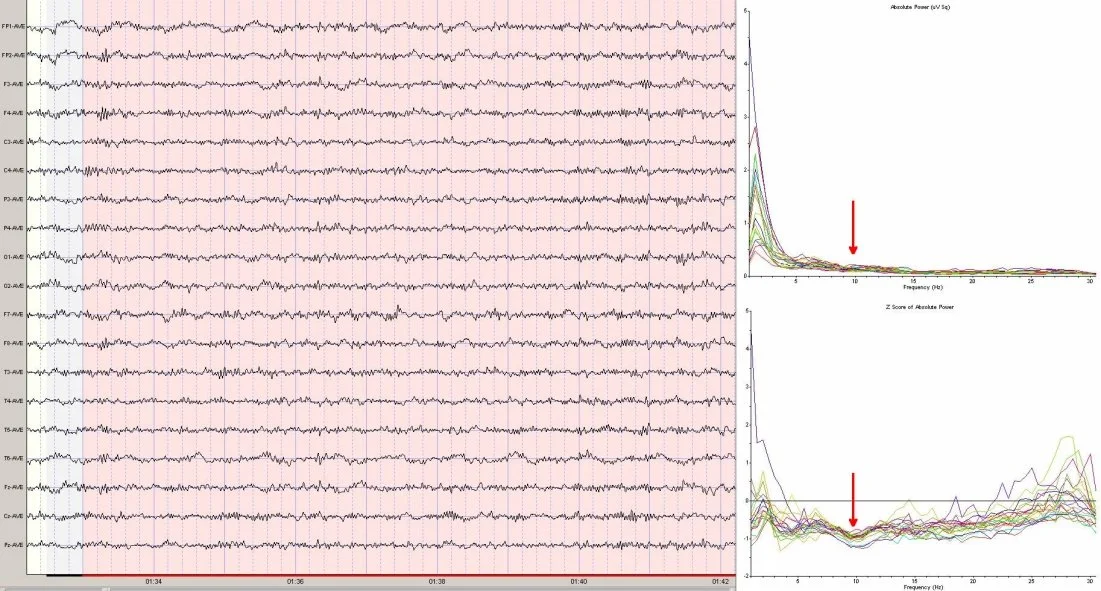

What is missing from the record is any organized, dominant alpha pattern—normally seen during an eyes closed recording. For adults, the alpha peak frequency is normally around 10hz. The following spectra graphs show where the alpha peak would be, if it were present. Additionally, the Z score (statistical) spectra graph shows a dip instead of a peak, further accentuating the absence of a normal alpha pattern.

Attenuated alpha has been shown to be associated with anxiety in some persons, and may be a marker for emotional trauma. However, the automated report fails to register this pattern. No protocol is recommended by the report for addressing this issue. Eyes closed, posterior alpha training has been found to be helpful for these individuals.